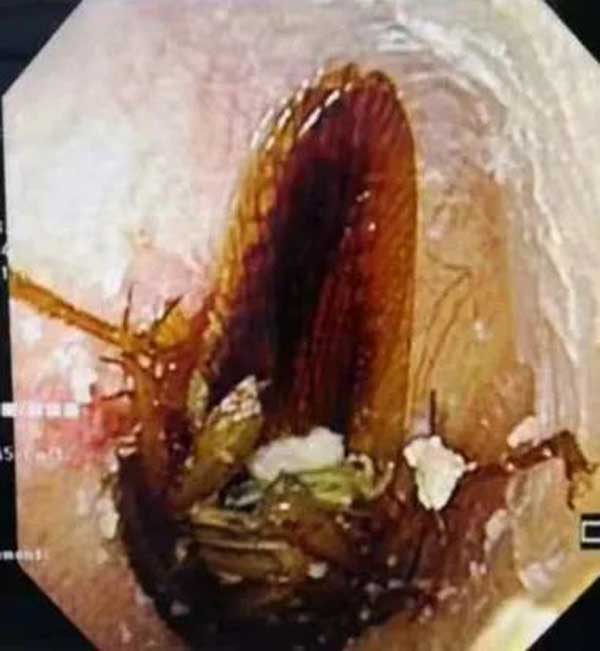

跑进耳朵里的小飞虫

次日一大早,3岁的阳阳就被妈妈带到了蜜桃视频 耳鼻喉科。经过检查,跑进阳阳右耳朵里的是一只小飞虫,所幸虫子位置不深。在安抚了阳阳的情绪后,副主任李莉萍用镊子小心地夹出了一只指甲盖大小的活体飞虫。她说:“幸亏孩子没有用力掏耳朵,不然很可能造成鼓膜穿孔,影响孩子听力。”